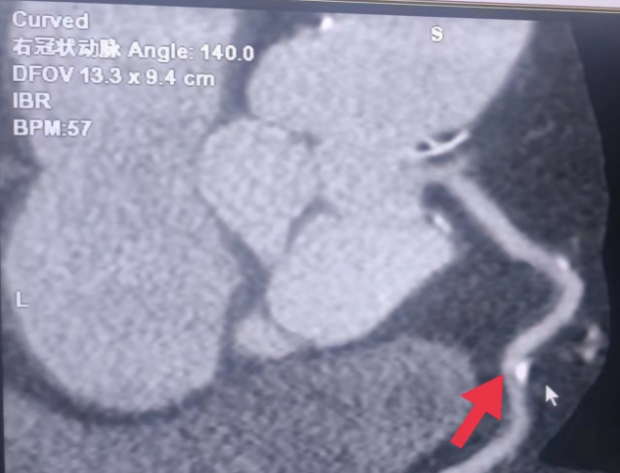

01**女士,70岁

2023年8月6日在邯郸仁泰东区体检冠脉CTA检查提示:左冠前降支近段钙化斑块,局部管腔轻微狭窄;中段混合斑块,局部管腔达重度狭窄(约90%左右);回旋支起始段钙化斑块,局部管腔轻度狭窄;右冠多发钙化斑块,近段轻微狭窄,中段轻度狭窄。首次回访2023年8月8日,通知客户去三甲医院进一步检查和治疗。2023年9月9日跟踪回访,客户家属反馈,已在邯郸某三甲医院完成支架手术,现服药治疗。